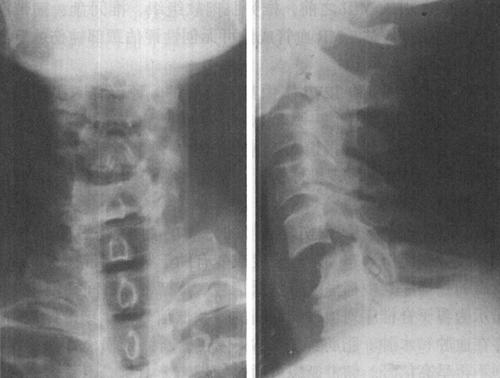

图7-1 正常颈椎X线侧位片:正常颈椎前、中、后三柱连线光滑连续,中、后柱连线之间为脊髓所在

图7-2 C5以上前脱位,中、后柱连线显示在C5水平处明显狭窄,表明颈髓在此处受压

图7-12a 颈段脊髓横断性损伤。颈椎正侧位片:C5以上前脱位,该水平段椎管狭窄,可推测脊髓受压迫